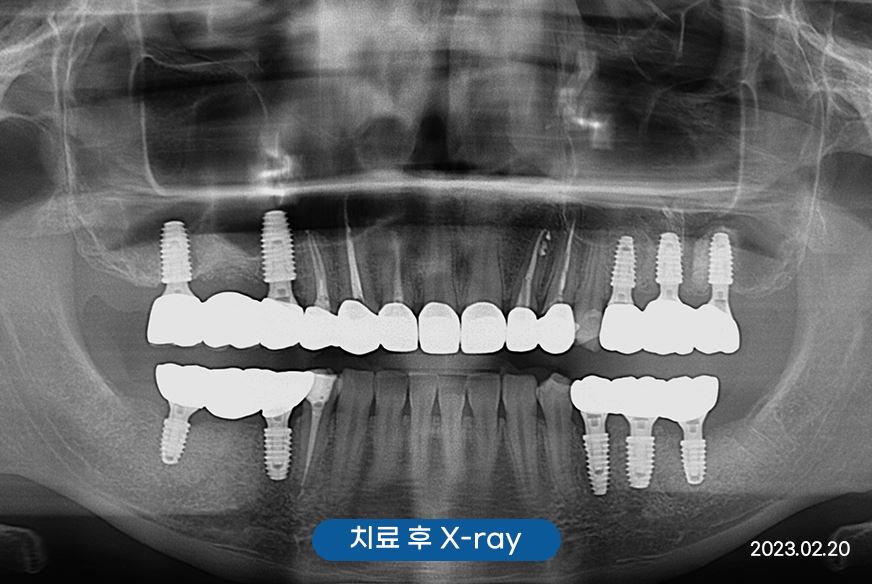

양쪽 위 아래 어금니 임플란트로

계획을 세우게 되었습니다.

부러진 어금니로 인해

많이 불편했었는데

임플란트 후 이제 편안하게

식사를 할 수 있어

건강도 더 좋아진 것 같아요!

앞니의 경우 충치가 꽤 진행되어

보철로 함께 마무리 해드렸는데